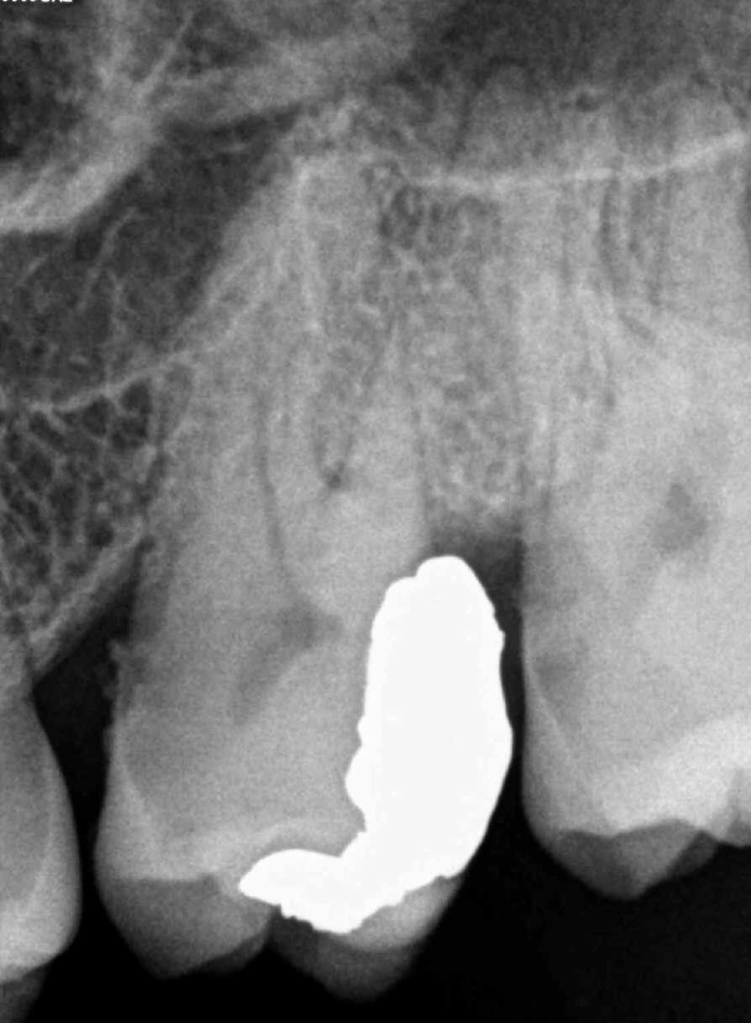

Pulpotomía biodentine + reco preendio